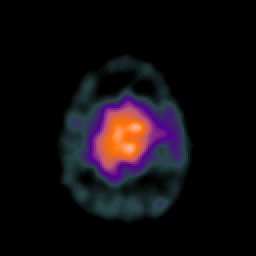

SPECT TC Study #2 -- Slice #47

[Home][Help][Clinical][Tour 1][Tour 2][Tour 3] Slice 47